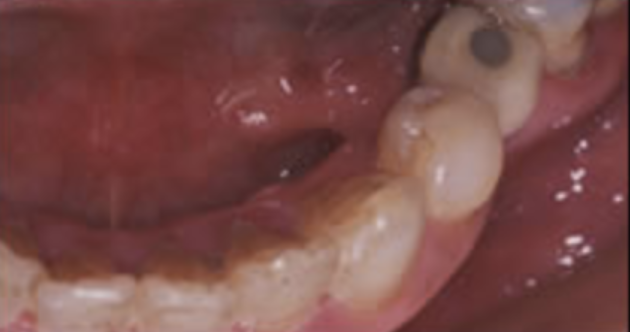

治療前

初診時での正面・側方・咬合面観を示します。